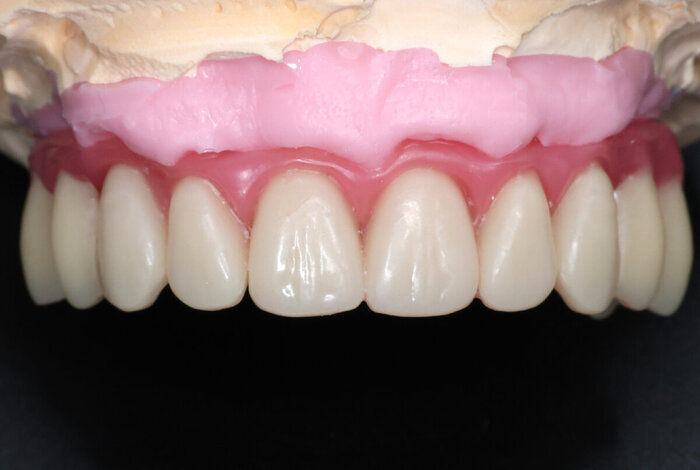

Протез FP2

Вариант 2 - зубы нормального размера, но десна розовая в наличии.

Протез FP3

Постановка на воске.

Временный протез "всё на 4-х", постановка на воске

На фото выше - воск. Протез временный будет поизящнее. Постоянный, когда до него дойдёт, ещё более гладкий и аккуратный получится.